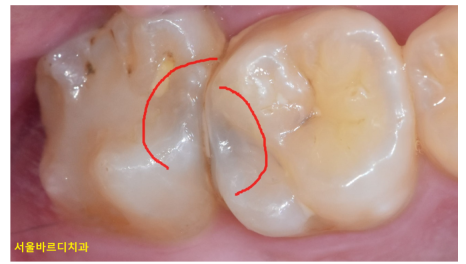

간혹 씹는 힘에 문제가 있을 때

시림이나 통증으로 느껴질 수 있는데요.

치료한 이가 맞물릴 때 너무 빨리 닿는 경우

아프거나 시릴 수 있습니다.

250120 특정 치아가 먼저 닿으면 힘이 골구로 가해지지 않아 아플 수 있어요